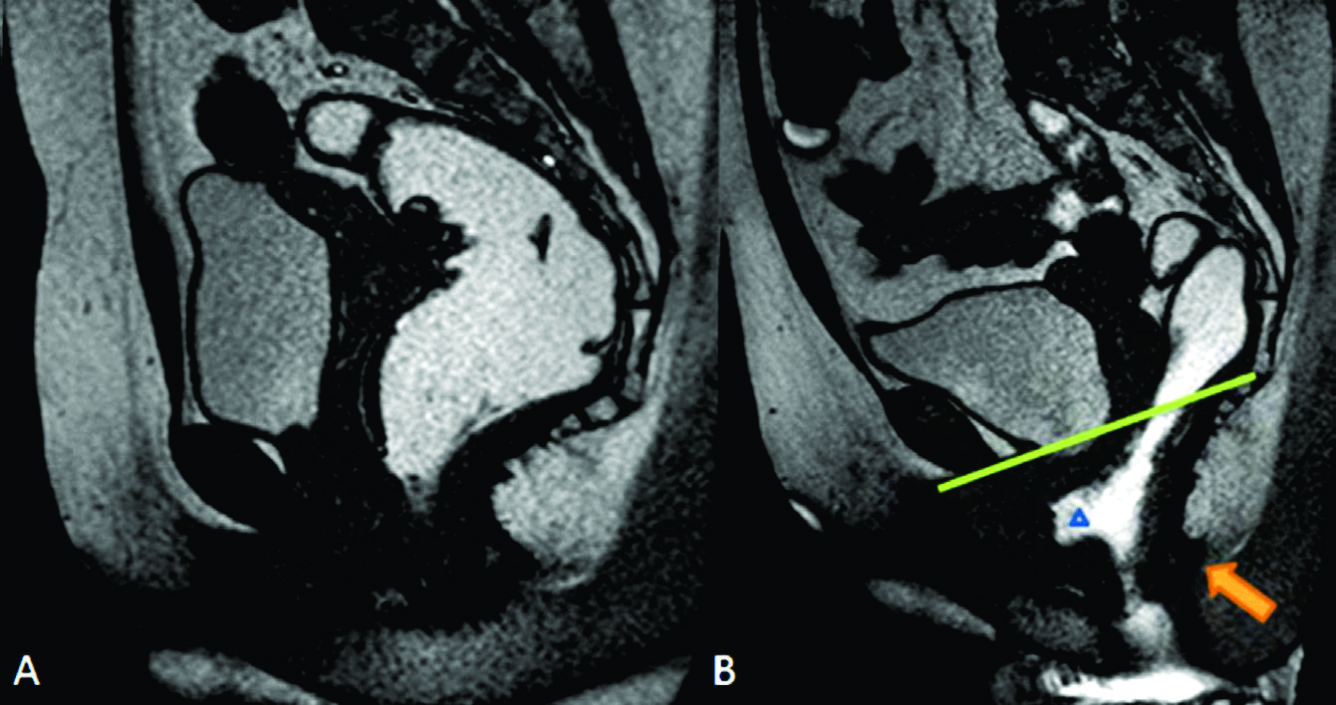

Figura 7

Rectocele anterior y cistocele.

Imágenes TRUE FISP de alta resolución en el plano sagital a nivel de la línea media de una mujer durante A) el reposo y durante B) la defecación. En B se observa angulación caudal del plano del elevador (flecha naranja), rectocele anterior (triangulo) y cistocele con hipermotilidad uretral (punteado azul en B).